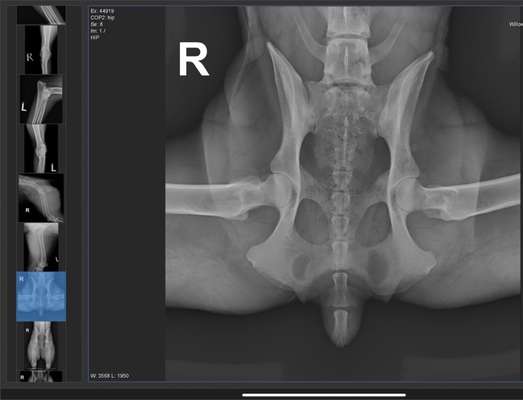

Hab Röntgen Bilder für euch. Lagerung nicht perfekt und bin gespannt was der Doktor zum LÜW sagt...

2